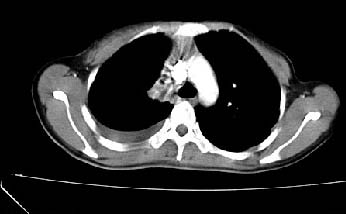

以下是引用zjzjr在2007-3-15 13:31:00的发言:[br]支持楼主诊断.右侧中央型肺癌伴右上叶节段性肺不张、胸腔积液、纵隔淋巴结转移。

以下是引用zyx168在2007-3-15 17:05:00的发言:[br]右侧中央型肺癌伴右上叶节段性肺不张、胸腔积液、纵隔淋巴结转移。